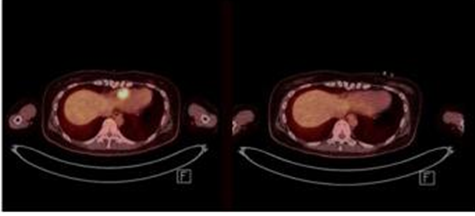

이에 지난 4월 이후 국내 병원 중 처음으로 CAR-T 치료제 생산부터 투여 후 환자 치료까지 전 과정을 준비해 백혈병 환자를 치료 중인 서울대병원이 나섰다. 서울대병원에서 치료 중인 환자 중에는 골수 외 재발 환자도 포함되어 있었고, 백혈병 종괴가 사라지는 효과를 보이기도 했다.

이러한 치료 성적을 기반으로 CAR-T 치료가 필요하지만 보험 급여가 되지 않는 25세 이하 미세백혈병 및 골수 외 재발 환자들에게 치료의 기회를 제공하기 위해 보건복지부에 임상 연구 환자 수 확대를 요청했고 최근 심의에서 통과됐다.